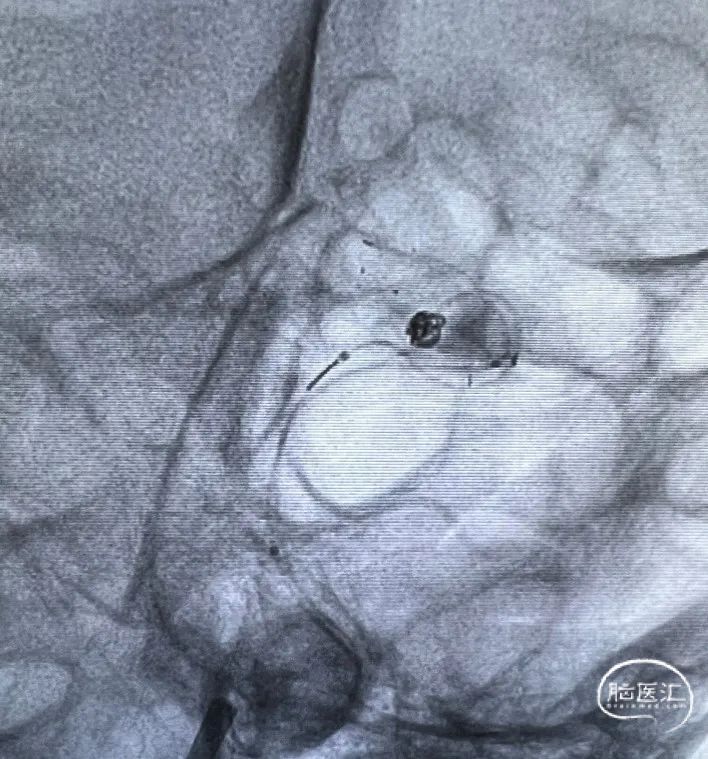

大脑中动脉下干置入3*24mm Atlas支架,使用Target 360 Ultra 2mm*4cm;弹簧圈栓塞动脉瘤。行造影观察血流通畅。(如下动态影像)

穿第一枚支架网眼于上干置入3*15mm Atlas支架

使用第二枚弹簧圈Target 360 Nano 1.5mm*4cm栓塞动脉瘤,造影显示动脉瘤瘤腔内有滞留,考虑到是未破裂动脉瘤,故结束手术。(如下动态影像)

术后造影

治疗后正位减影造影,动脉瘤基本致密栓塞,患者术后无明显不适,术后阿司匹林,波立维双抗。目前一般状况良好。(如下动态影像)